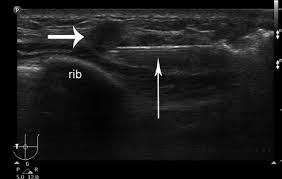

В нашей клинике мы предлагаем безоперационный метод удаления фиброаденом при помощи вакуумно-аспирационной резекции. Доступ осуществляется через прокол кожи 2-3 мм, а сама ткань новообразования удаляется под УЗ контролем.

На рисунке показано подведение инструмента (тонкая стрелка) к образованию (короткая стрелка) молочной железы.

Методика безопасна, является альтернативно секторальной резекции при доброкачественных образованиях молочных желез, обладает низким процентом осложнений и хорошо переносится пациентами.